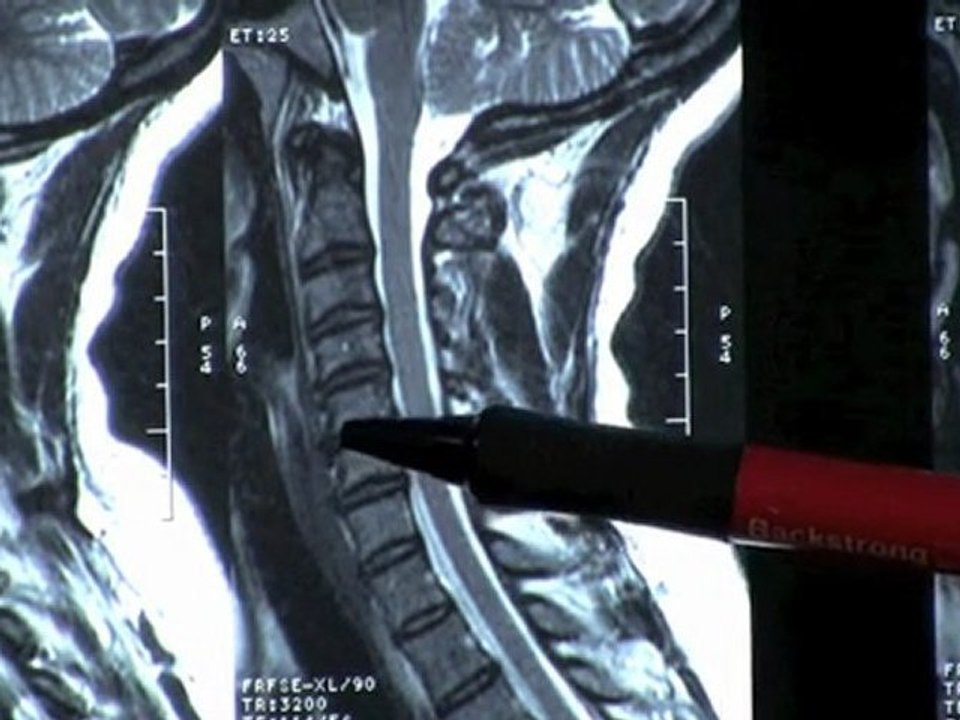

Low Back MRI scan explaining low back pain, herniated and degenerated discs, & spinal decompression physical therapy & chiropractor treatment 8:06

Low Back MRI scan explaining low back pain, herniated a...